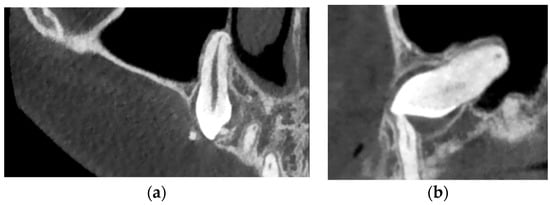

Figure 2.

(a) The right maxillary canine also has a root DL, presenting a “hook” bend towards the mesial in the apical third of the root. (b) “Bull’s eye” phenomena highlighted in the sagittal section.